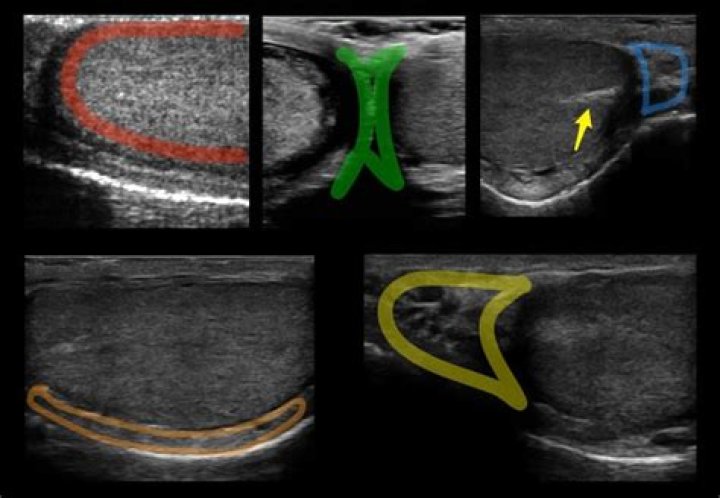

Sonographically, the head of the epididymis is better depicted in the longitudinal view than in others. It is an isoechoic or slightly hypoechoic structure with medium-level echoes. Usually, the body of the epididymis is not identified at sonography in healthy adults. Sometimes, the epididymal tail is seen.

The head is the largest and most prominent part and is found at the superior pole of the testis. The head of the epididymis measures approximately 5-12 mm in length and may have a small projection called the appendix of the epididymis 3. The tail of the epididymis is found at the inferior pole of the testis 3.